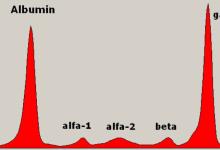

Markers of hand OA severity included a modified five-grade Kellgren/Lawrence score (for overall severity), radiographic evidence of joint erosion, chondrocalcinosis of the triangular fibrocartilage complex (TFCC), presence of symptomatic hand OA, and presence of clinical hand OA (presence of Heberden's nodes plus radiographic chondrocalcinosis of the TFCC).